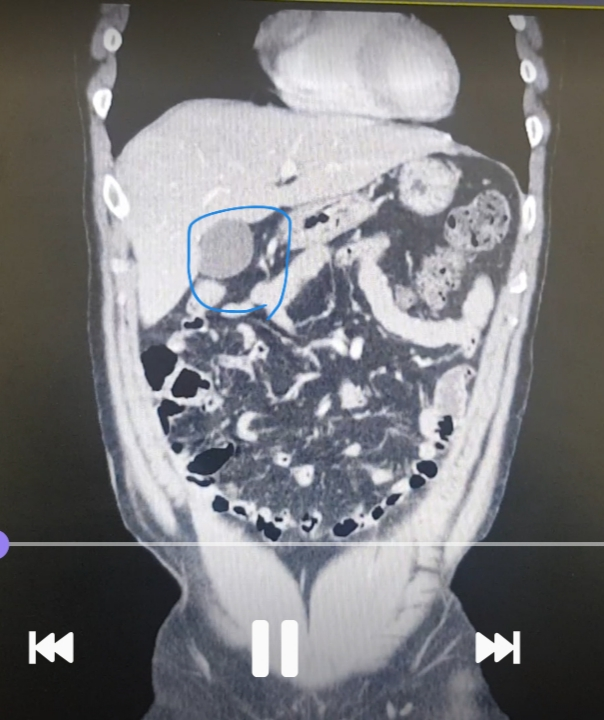

영상에서 이부분이 뭔지 알려주세요

간밑에 이게 뭔지 알려주세요

그리고 다른 질환이 보이는지 보이는거 알려주세요

특히 좌측복부 게실염 우측신장 물혹 있나봐주세요

우선 파란색으로 표시하신건 담낭입니다.

우측 신장에 물혹은 보이지 않습니다.

게실염은 제가 평소에 복부CT를 보는 의사가 아니라서 여부를 잘 모르겠습니다.